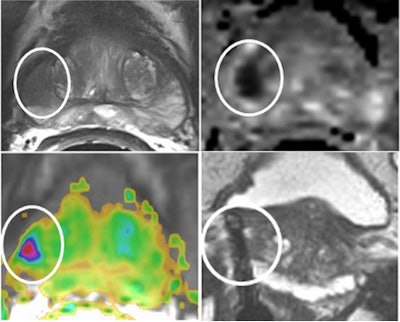

A multiparametric approach promises improved detection and characterization of prostate cancer. He thinks the way forward is T2-weighted diffusion and dynamic imaging. Future perspectives in prostate cancer imaging look set to be interesting, and he welcomes the day when all patients will have an MRI examination before they have a biopsy. Contrast agents such as iron oxide particles (small nanoparticles that travel to the lymph nodes) promise to assist in the detection of small (2 mm) lymph nodes. Barentsz hopes for more precise diagnosis of prostate cancer, which he believes will be achieved with the use of MR-ultrasound fusion and minimally invasive therapy by treating localized tumors with high-intensity focused ultrasound under MR guidance.